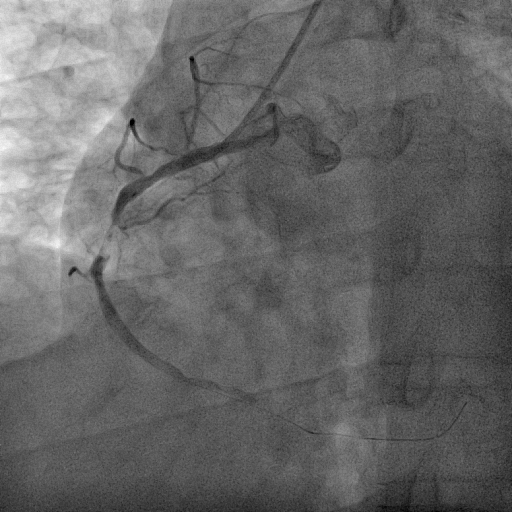

We decided to proceed with the primary percutaneous coronary angioplasty via right radial access by using the 5F JR 3.5 guiding catheter . We used Run through NS floppy wire for crossing culprit lesion to distal RCA but TIMI flow 0. We used micross 1.0 balloon for just cross the lesion and tracking balloon over the lesion . Then distal segment properly seen. Pre dilatation not done due to acute lesion and high chance of thrombus dislodgement and distal embolization . Direct stent 3.50 x 42 mm was implanted in proximal RCA to Mid RCA at 14 atmosphere pressure. Stent was well apposed and final result angiography was excellent and TIMI III flow without residual lesion and no distal embolization. the procedure done without any complications. Total Inj. heparin 10000 unit given and ACT was 298 sec.

SHAHIDUL ISLAM_(S8_F1-57).avi

SHAHIDUL ISLAM_(S12_F1-23).avi

SHAHIDUL ISLAM_(S14_F1-46).avi